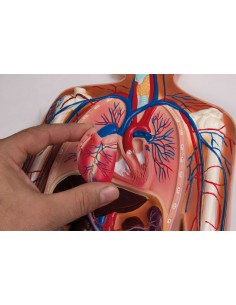

Dal cranio in 22 parti con incastri magnetici ai modelli di colonna vertebrale, da quelli di articolazioni a quelli di cuore, ogni pezzo della nostra collezione è progettato per un’immersione totale nello studio dell’anatomia umana. I nostri modelli, realizzati tramite scansioni di ossa vere, garantiscono un’esperienza tattile autentica e una fedeltà di peso quasi identica agli originali.

Essenziali per studenti e professionisti, i nostri modelli anatomici sono strumenti didattici che permettono di osservare le strutture anatomiche con precisione, eliminando la necessità di dissezioni o studi invasivi. Sono inoltre utili per spiegare ai pazienti le patologie, rendendo la comunicazione più efficace e risparmiando tempo prezioso.